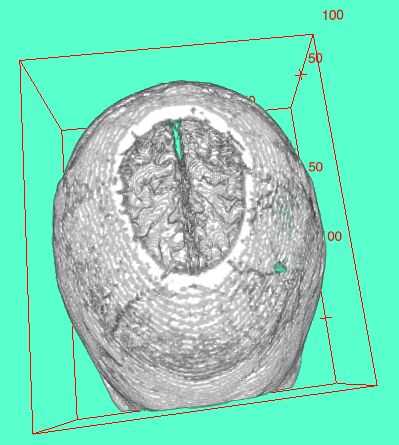

Ahora si sólo tuviera una impresora 3D... â º

Creo que hay algo sobre una imagen que se generó teniendo cerebro 'rodajas' se imprime en rebanadas - jaja pero en plástico y no cerebro (aunque sería más fácil estudiar!).